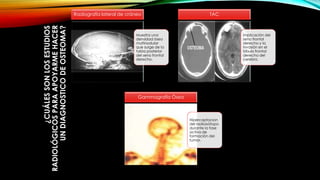

¿CUÁLESSONLOSESTUDIOS

RADIOLÓGICOSPARAAPOYARMEHACER

UNDIAGNOSTICODEOSTEOMA?

Muestra una

densidad ósea

multinodular

que surge de la

tabla posterior

del seno frontal

derecho.

Radiografía lateral de cráneo

implicación del

seno frontal

derecho y la

invasión en el

lóbulo frontal

derecho del

cerebro.

TAC

Hipercaptacion

del radioisótopo

durante la fase

activa de

formación del

tumor.

Gammagrafía Ósea